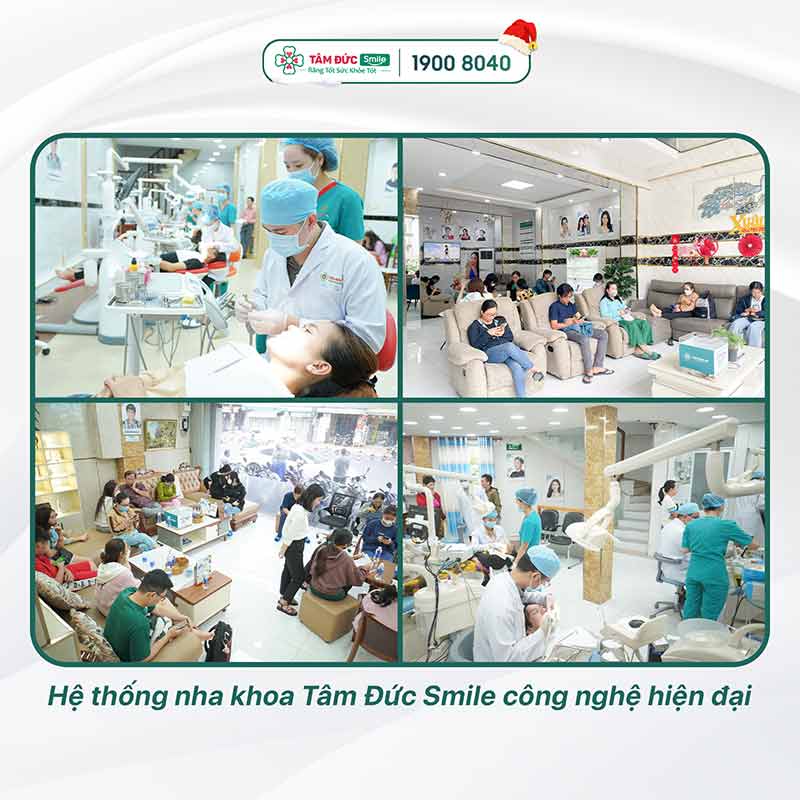

Tâm Đức Smile là địa chỉ mà Quý khách không thể bỏ qua khi có nhu cầu thăm khám sức khỏe răng miệng. Tâm Đức Smile quy tụ bác sĩ tay nghề cao, trang bị hệ thống máy móc tiên tiến, đã điều trị hàng trăm ca nhổ răng khôn thành công. Đến với Tâm Đức Smile, Quý khách hoàn toàn có thể yên tâm, vì nhổ răng khôn được hạn chế xâm lấn, không gây bất kỳ biến chứng nào.